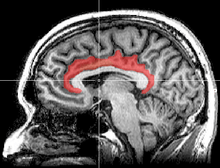

![]() Medial surface of left cerebral hemisphere, with cingulate gyrus and cingulate sulcus highlighted. | |

The cingulate cortex, a part of the limbic cortex, is a part of the brain situated in the medial aspect of the cerebral cortex. The cingulate cortex includes the entire cingulate gyrus, which lies immediately above the corpus callosum, and the continuation of this in the cingulate sulcus. The cingulate cortex is usually considered part of the limbic lobe.